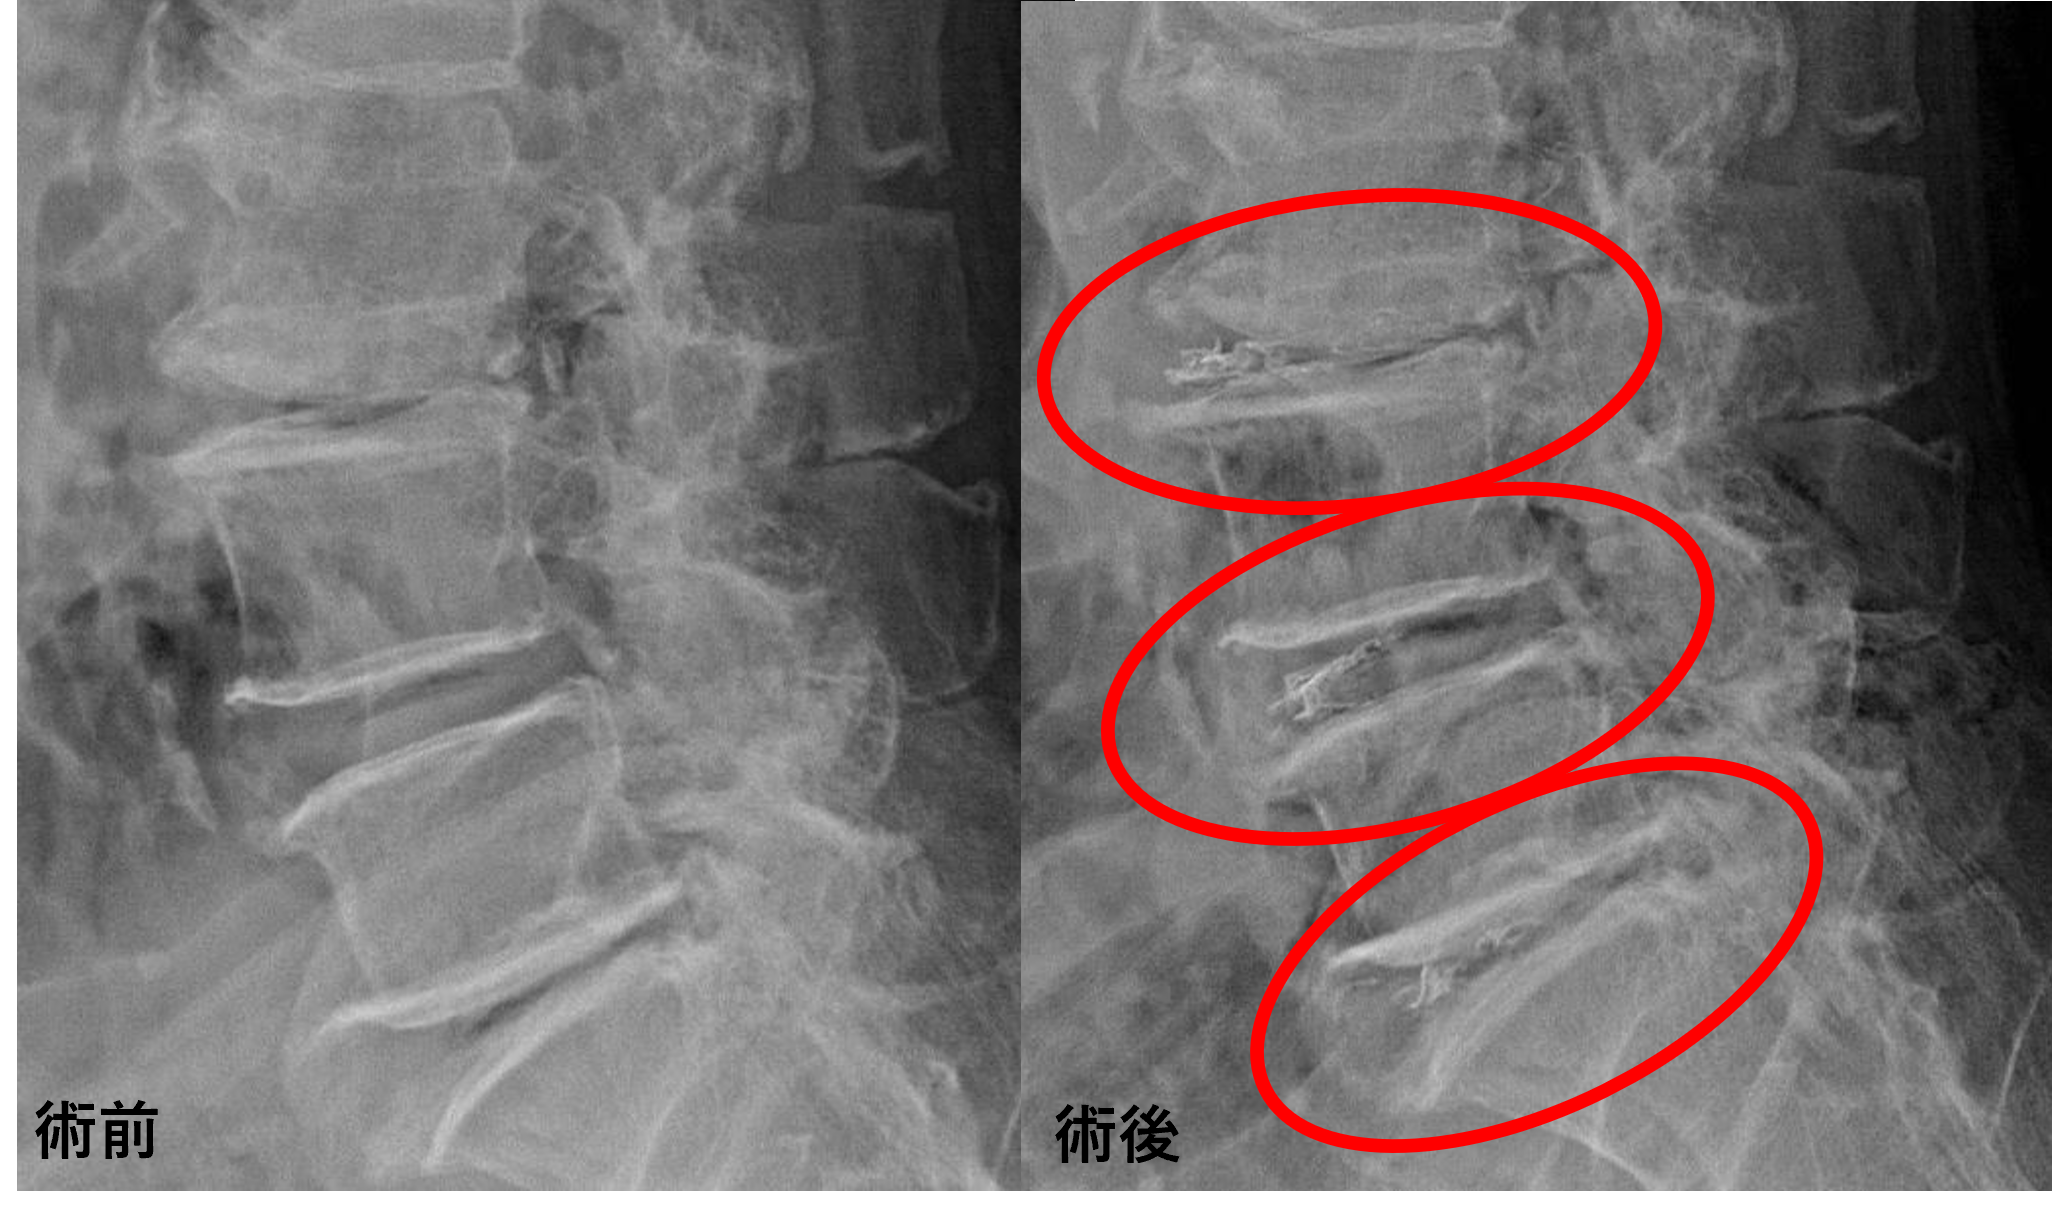

画像及び所見について

- L1/2、2/3、3/4、4/5 – 椎間板変性、膨隆、椎間孔狭窄

- L5/s – 椎間板変性、椎間板ヘルニア、椎間孔狭窄

以上のことが画像上認められました。

L3/4、4/5、5/sの椎間板所見による脊柱管の圧排が、症状の原因の可能性が高い。

L1/2、2/3は症状との対比から影響は少なそう。

患者様と相談の元、L3/4、4/5、5/sにセルゲル法を施行